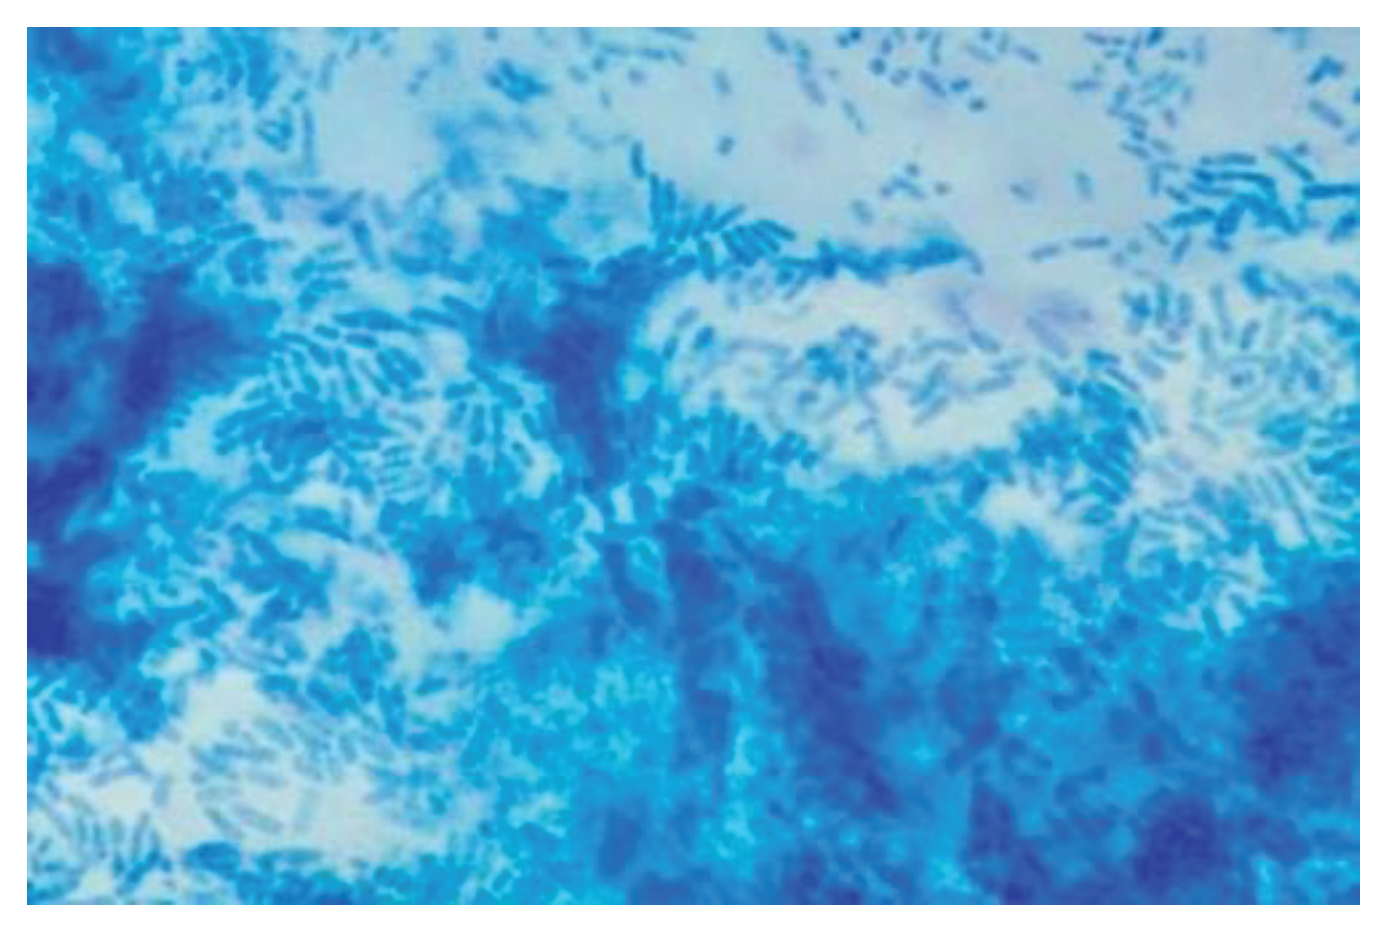

Secretions were present in 81 patients (81%) in both groups, of which 42 in the control group (84%) patients and 39 in the treated group (78%). The ciliary motility study carried out in all patients showed presence of a ciliary beat in 61 patients (61%), of which 29 (58%) in the control gropu and 32 (64%) in the treated group. Ciliary motility was observed in vivo with a phase-contrast light microscope and was considered normal in patients who had a ciliary beat for a time longer than 10 minutes. (Table 3). In all enrolled patients, cytological sampling was performed at the level of the mucosa of the middle third of the inferior face of the inferior turbinate. The sampling was air-fixed and stained by the May Grunewald Giemsa method. The presence of biofilm is characterized by the presence of cyan-colored areas.

Detection of biofilms on the nasal specimen saw a 12.8% increase in presence in the control group, while it decreased by 66.75% in the treated group. (Table 12) (Figure 2)

Figure 2. Biofilm in nasal specimen (May Grundwald Giemsa).